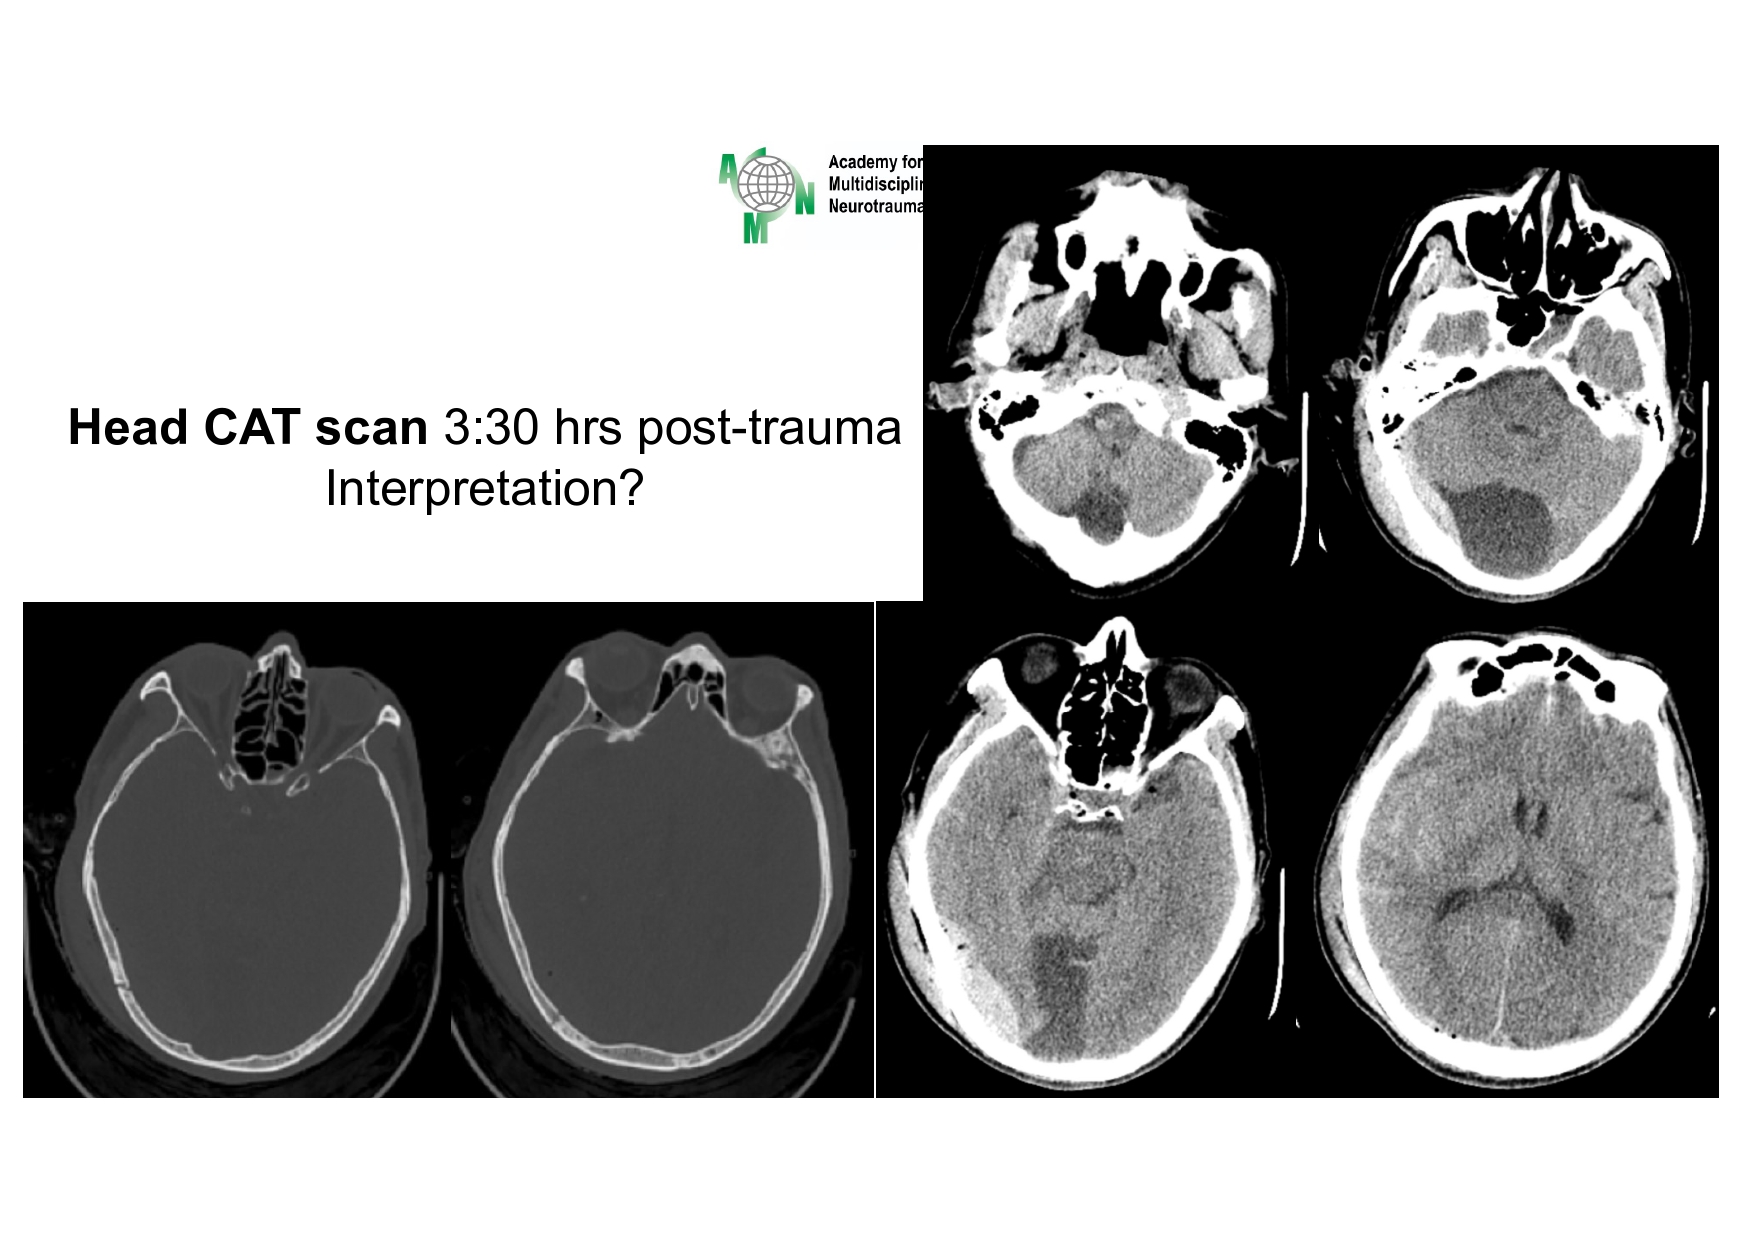

| 08:40 - 09:20 | Diagnosis of skull base trauma Post-traumatic CSF leakage | Assoc. Prof. Dong Van He Assoc. Prof. Kieu Dinh Hung | |

| 10:20 - 10:50 | Special Lecture II “Shock room management” | Prof. Harald Widhalm | |

| 11:05 - 12:00 | Interactive Case Demonstration and Discussion I ~20 minutes each, (5 minutes presentation followed by 15 minutes discussion) Practicals: How I am doing it? Participants present case presentations about how they do it? The faculty comment on and discussion. 1. ICP management: How I am doing it? - Assoc. Prof. Duong Dai Ha 2. CSF leakage management: How I am doing it? - Assoc. Prof. Nguyen Thanh Bac | Prof. Christian Matula International & local faculties Participants | |

| 13:00 - 13:30 | Special Lecture III Polytraumatized Patients having brain trauma – How to handle it? | Prof. Harald Widhalm | |